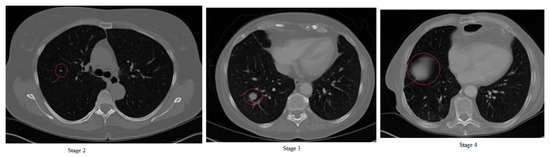

4. Tx Stages of Lung Cancer of Our Double CDNN

After defining, training and testing our network (Section 3.2), we used the topologies of the regular and double CDNN in experiments with an additional dataset from 35 patients diagnosed with lung cancer in stages 2, 3 and 4 (images obtained from the medical hospital in Tetovo, Macedonia). Since it is difficult to obtain images in stages 0 and 1, we found 35 patients whose possibility of cancer was diagnosed in stage 2 and recorded up until late stage 4. In Figure 7, we can see example CT images of stages 2, 3 and 4 of lung cancer.

Figure 7.

Stages 2, 3 and 4 of lung cancer.

From CT scan images, doctors can diagnose the stage only by using the size of the tumor (and in some cases the position of the tumor). Stage 2 (first image in Figure 7) shows the tumor in red circle on the left side, which in real size is around 4 cm. Stage 3 (second image in Figure 7) shows the cancer in red circle. In this stage, the tumor is larger than 4 cm and is in the middle of the lung and/or going towards the outer parts of the body. We can see in the second image in Figure 7 that the tumor is in late stage 3 since it leans towards the outer parts of the lungs. Stage 4 is in the third image in Figure 7 and we can see that the size of the tumor is covering large portions of the lung and is almost in the outer parts of the body and lung. This outer part of the lung is called area 1 and if the tumor is in this area (shown with red circle in the third image in Figure 7), it means that the cancer is terminal.